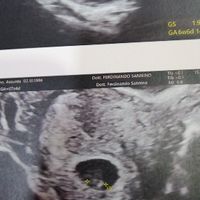

Metodo Ramzi pareri

Assia, Il 15 Febbraio 2019 alle 20:40

Ciao ragazze😀😀 Oggi a 7+4 ho fatto la mia prima ecografia. Secondo voi, secondo il metodo Ramzi, è maschio o femmina?